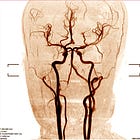

Brain death imaging tests are unreliable (INDex study)

To help make the diagnosis of brain death, specialized brain imaging tests are endorsed in many U.S. hospitals’ policies for patients who cannot complete an apnea test or other key aspects of the exam.